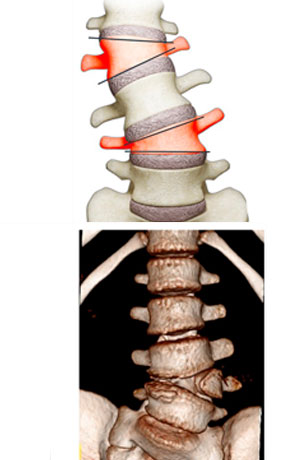

La escoliosis congénita ocurre porque las vértebras no se forman como deberían mientras el bebé crece en el útero.

Las vértebras son los huesos pequeños que componen la columna vertebral; son similares a una torre de bloques de construcción. Algunos de estos huesos pequeños podrían faltar, o algunos de ellos podrían no haberse formado completamente, lo que puede causar que la columna vertebral se curve a medida que crece.

Este tipo de escoliosis ocurre durante el desarrollo fetal. Se provoca por una malformación congénita en la columna vertebral:

Fallo en la formación normal de las vértebras.

Ausencia de vértebras.

falta de separación de las vértebrasértebras parcialmente formadas.

Falta de separación de las vértebras.